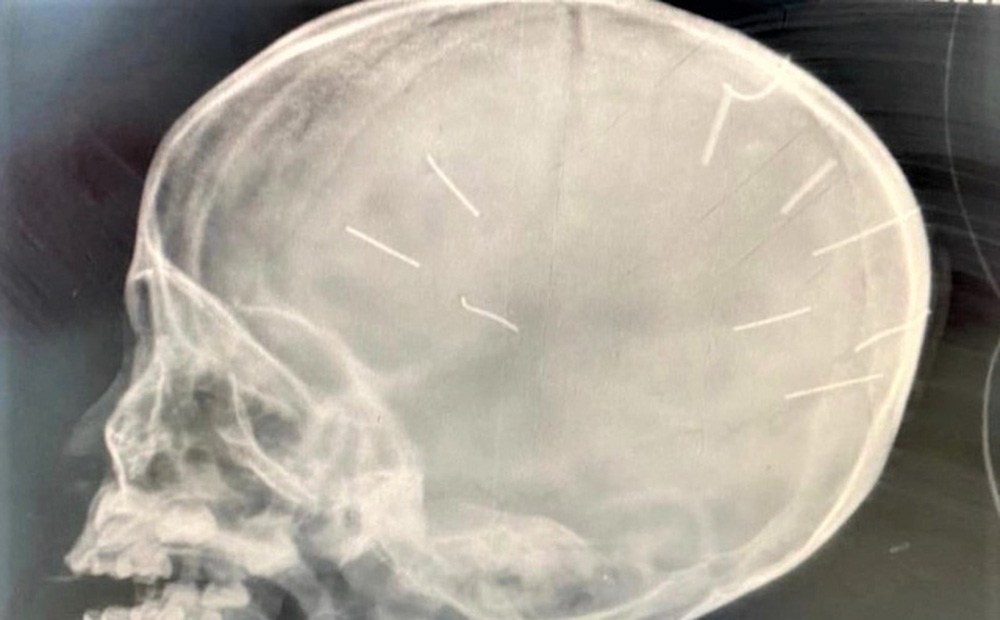

Ảnh phim chụp đinh trong đầu bé 3 tuổi.

Sau khi các bác sĩ tiếp nhận bệnh nhân, tiến hành đặt ống, chụp phim đã phát hiện 9 chiếc đinh trên phim chụp có hình ảnh cản quang trên hộp sọ. Trong quá trình kiểm tra, thăm khám, các bác sĩ phát hiện cánh tay phải của bé đã được bó bột trong 2 tuần.